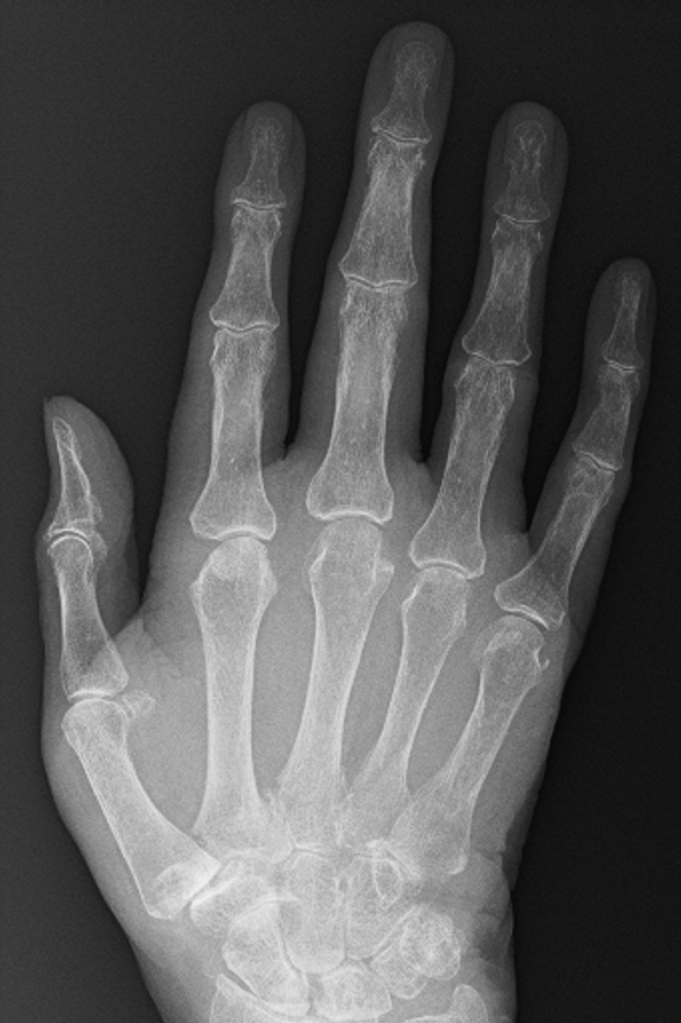

Loss of joint Space

In young patients, there are thick cartilage caps on the ends of the bones within the small joints of the hand. With age, these cartilage caps slowly wear from constant use, despite the body’s regenerative processes. A normal joint, therefore, has much less cartilage at 50 than at 20, and by the time people reach 80+ years, there is often very little cartilage left.

The GAP between the bones on an xray represents the space occupied by the cartilage, and it is very easy to predict how much cartilage is left in a joint simply by looking at the amount of space between the bones – the more space the more cartilage, and generally speaking the more healthy the joint.